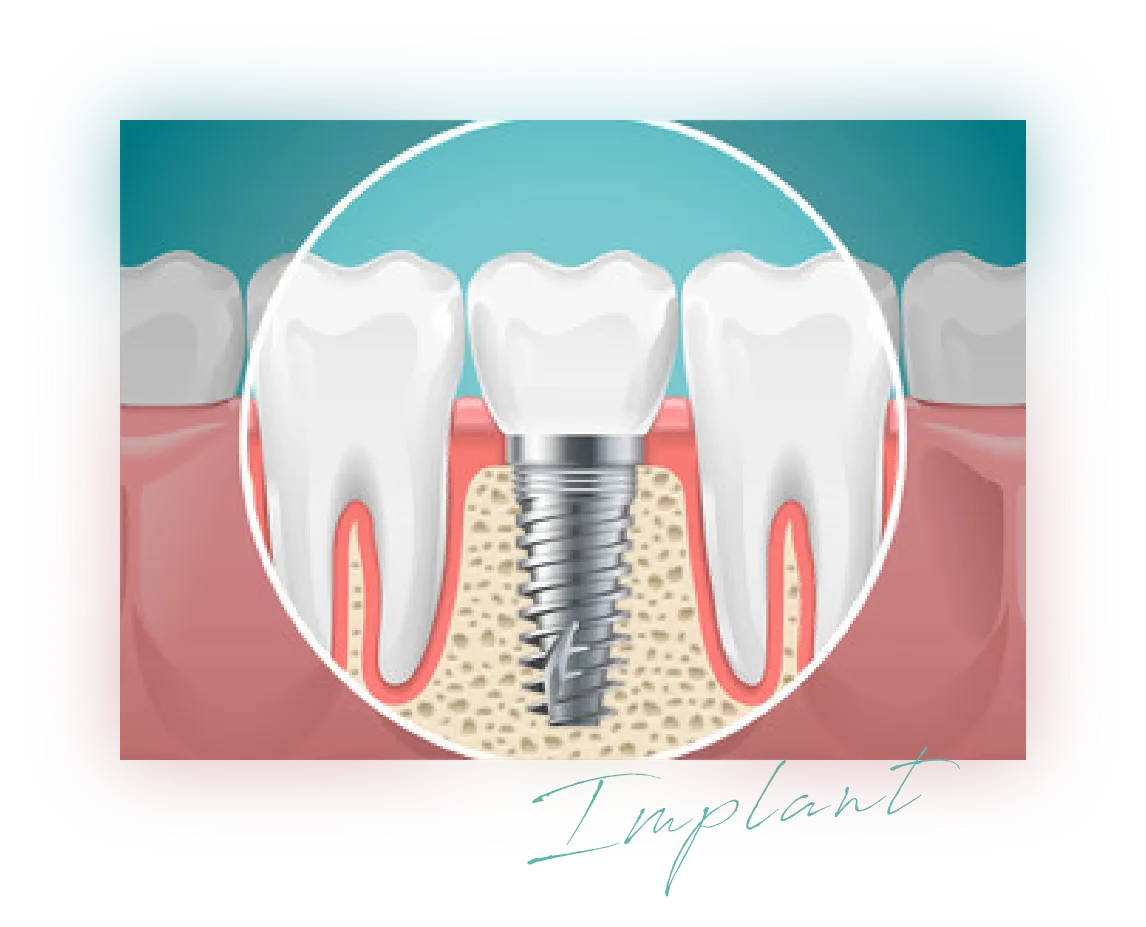

インプラントとは?

インプラント治療は、失った歯の代わりにインプラント(チタン製ネジのようなもの)を歯の根っことして埋め込み、人工の歯(被せ物)はめ込む外科手術です。

オールセラミックを用いた「自分の歯と変わらない見た目の自然さ」「噛む力の強さ」が魅力で、残った歯を傷つけず、見た目も感覚もまるでもともと自分の歯だったのかのような第2の永久歯に仕上がります。